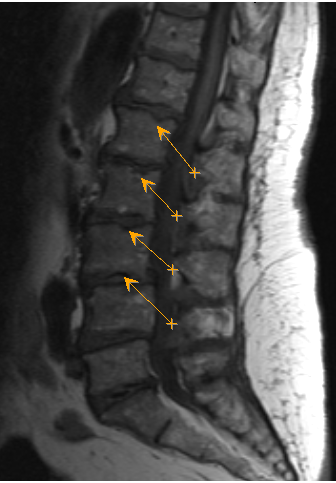

Грыжа Шморля

Делала на днях мскт печени с контрастом. ну видать они заодно и остальное посмотрели. Печень в норме. Но нашлы на позвоночнике Грыжи Шморля. Из инета не особо поняла к какому врачу с этим идти. Понятное дело что первый пункт это терапевт. Может у кого есть данная напасть? Поделитесь как с этим жить лечить и т.д.